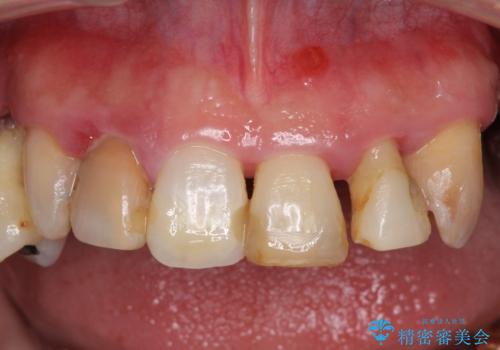

- 歯周病を放置したことで奥歯が抜け、前歯も痛くなってきたとのことで来院された患者様です。

奥歯はほとんどを抜歯しなければならない状態であり、抜歯をせずに済む歯も歯周外科処置や矯正治療を行う必要がある状態でした。

歯を抜かないといけない部分はインプラントとオールセラミッククラウンにより咬合を回復させ、歯周外科処置を行う歯については、同じくオールセラミッククラウンにて補綴治療を行うこととしました。